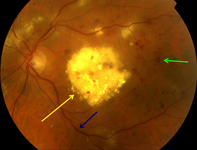

Non-proliferative diabetic retinopathy with macular oedema: exudate plaque (yellow arrow), cluster haemorrhage (green arrow), venous beading (blue arrow)

Courtesy of Moorfields Photographic Archive; used with permission